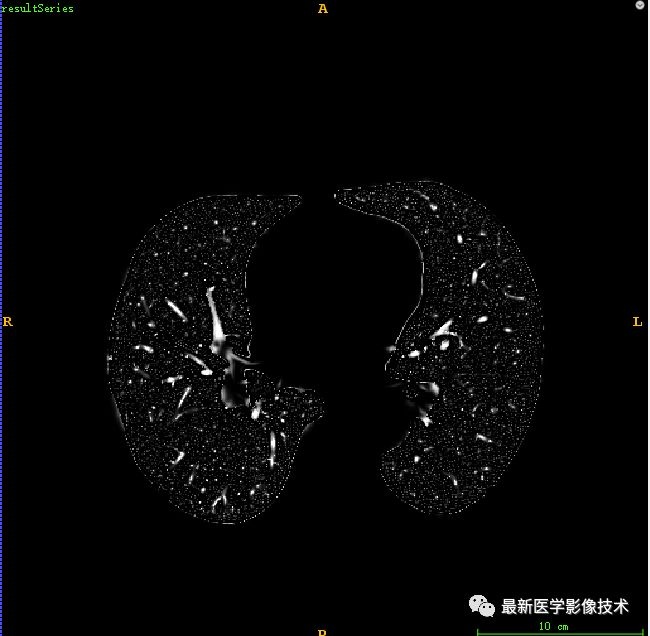

为了提高图像质量并增强血管区域的可见性,采用Hessian矩阵技术进行增强处理。增强后的血管区域图像显示为明亮的结构,并通过阈值分割方法提取出特征明显的血管区域图像。

通过对比度增强处理后得到的血管区域呈现出明显的明亮特征,在后续处理中我们采用了一种基于阈值的二值化方法对增强后的图像进行分割。具体而言,在完成上述操作后生成的结果中仅保留了具有显著特征的血管区域轮廓。这一过程能够有效地区分出不同类型的血管结构。